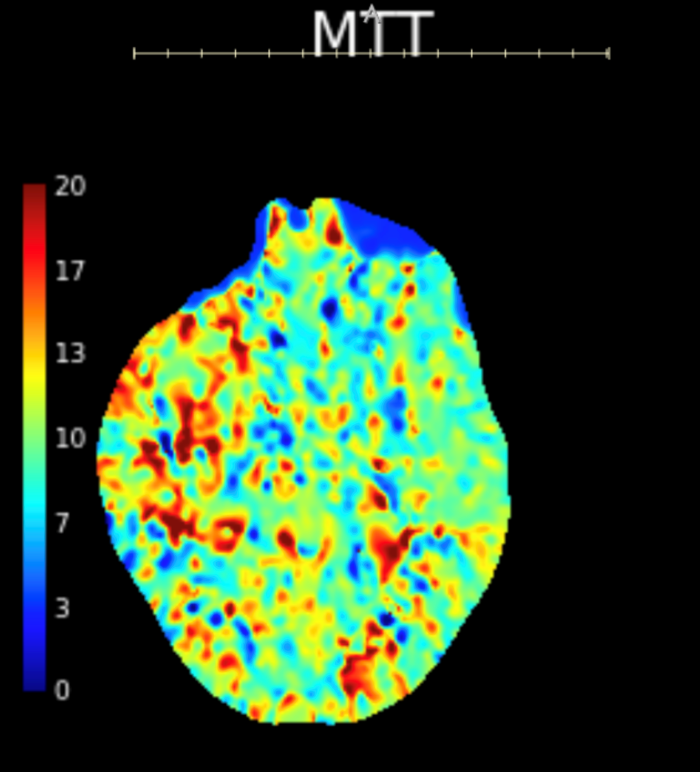

Initial objective data included T 37C, HR 85, RR 20, BP 153/109, spO2 98%. Glucose 102. Basic labs obtained and were unremarkable. Patient was rapidly taken to CT for stroke imaging. No contraindications to thrombolytics were identified. At 1708, noncontrast head CT showed no hemorrhage, but an abnormal hypodensity along the right middle cerebral artery concerning for an air embolus was visualized. CT angiogram head and neck was also suggestive of air embolus and CT perfusion brain demonstrated 27 mL of critical hypoperfusion at the right posterior middle cerebral artery distribution.

Figure 3: CT perfusion brain showing prolonged mean transit time in the right MCA distribution compared to the left MCA.